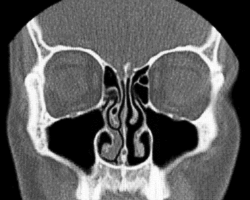

Conchae are composed of pseudostratified columnar, ciliated respiratory epithelium with a thick, vascular, and erectile glandular tissue layer.[4] The conchae are located laterally in the nasal cavities, curling medially and downward into the nasal airway. Each pair is composed of one concha in either side of the nasal cavity, divided by the septum.[4]

The superior conchae are smaller structures, connected to the middle conchae by nerve-endings, and serve to protect the olfactory bulb. The superior conchae attach to the ethmoid bone. The openings to the posterior ethmoidal sinuses exist under the superior meatus.[3] The sphenoid sinus ostium exists medial to the superior turbinate.[5]

The middle conchae are smaller but have the most complex anatomy of the nasal turbinates. They originate from the lateral edge of the cribriform plate of the ethmoid bone. They insert anteriorly into the frontal process of the maxilla and posteriorly into the perpendicular plate of the palatine bone.[6] There are three mutually perpendicular segments of the middle turbinate: from proximal to distal, there is the horizontal segment (axial plane), the basal lamella (coronal plane), and the vertical segment (sagittal plane). They project downwards over the openings of the maxillary and anterior and middle ethmoid sinuses, and act as buffers to protect the sinuses from coming in direct contact with pressurized nasal airflow. Most inhaled airflow travels between the inferior concha and the middle meatus.[3] In humans, they are usually as long as the little finger.

The inferior conchae are the largest turbinates, can be as long as the index finger in humans, and are responsible for the majority of airflow direction, humidification, heating, and filtering of air inhaled through the nose.[3]